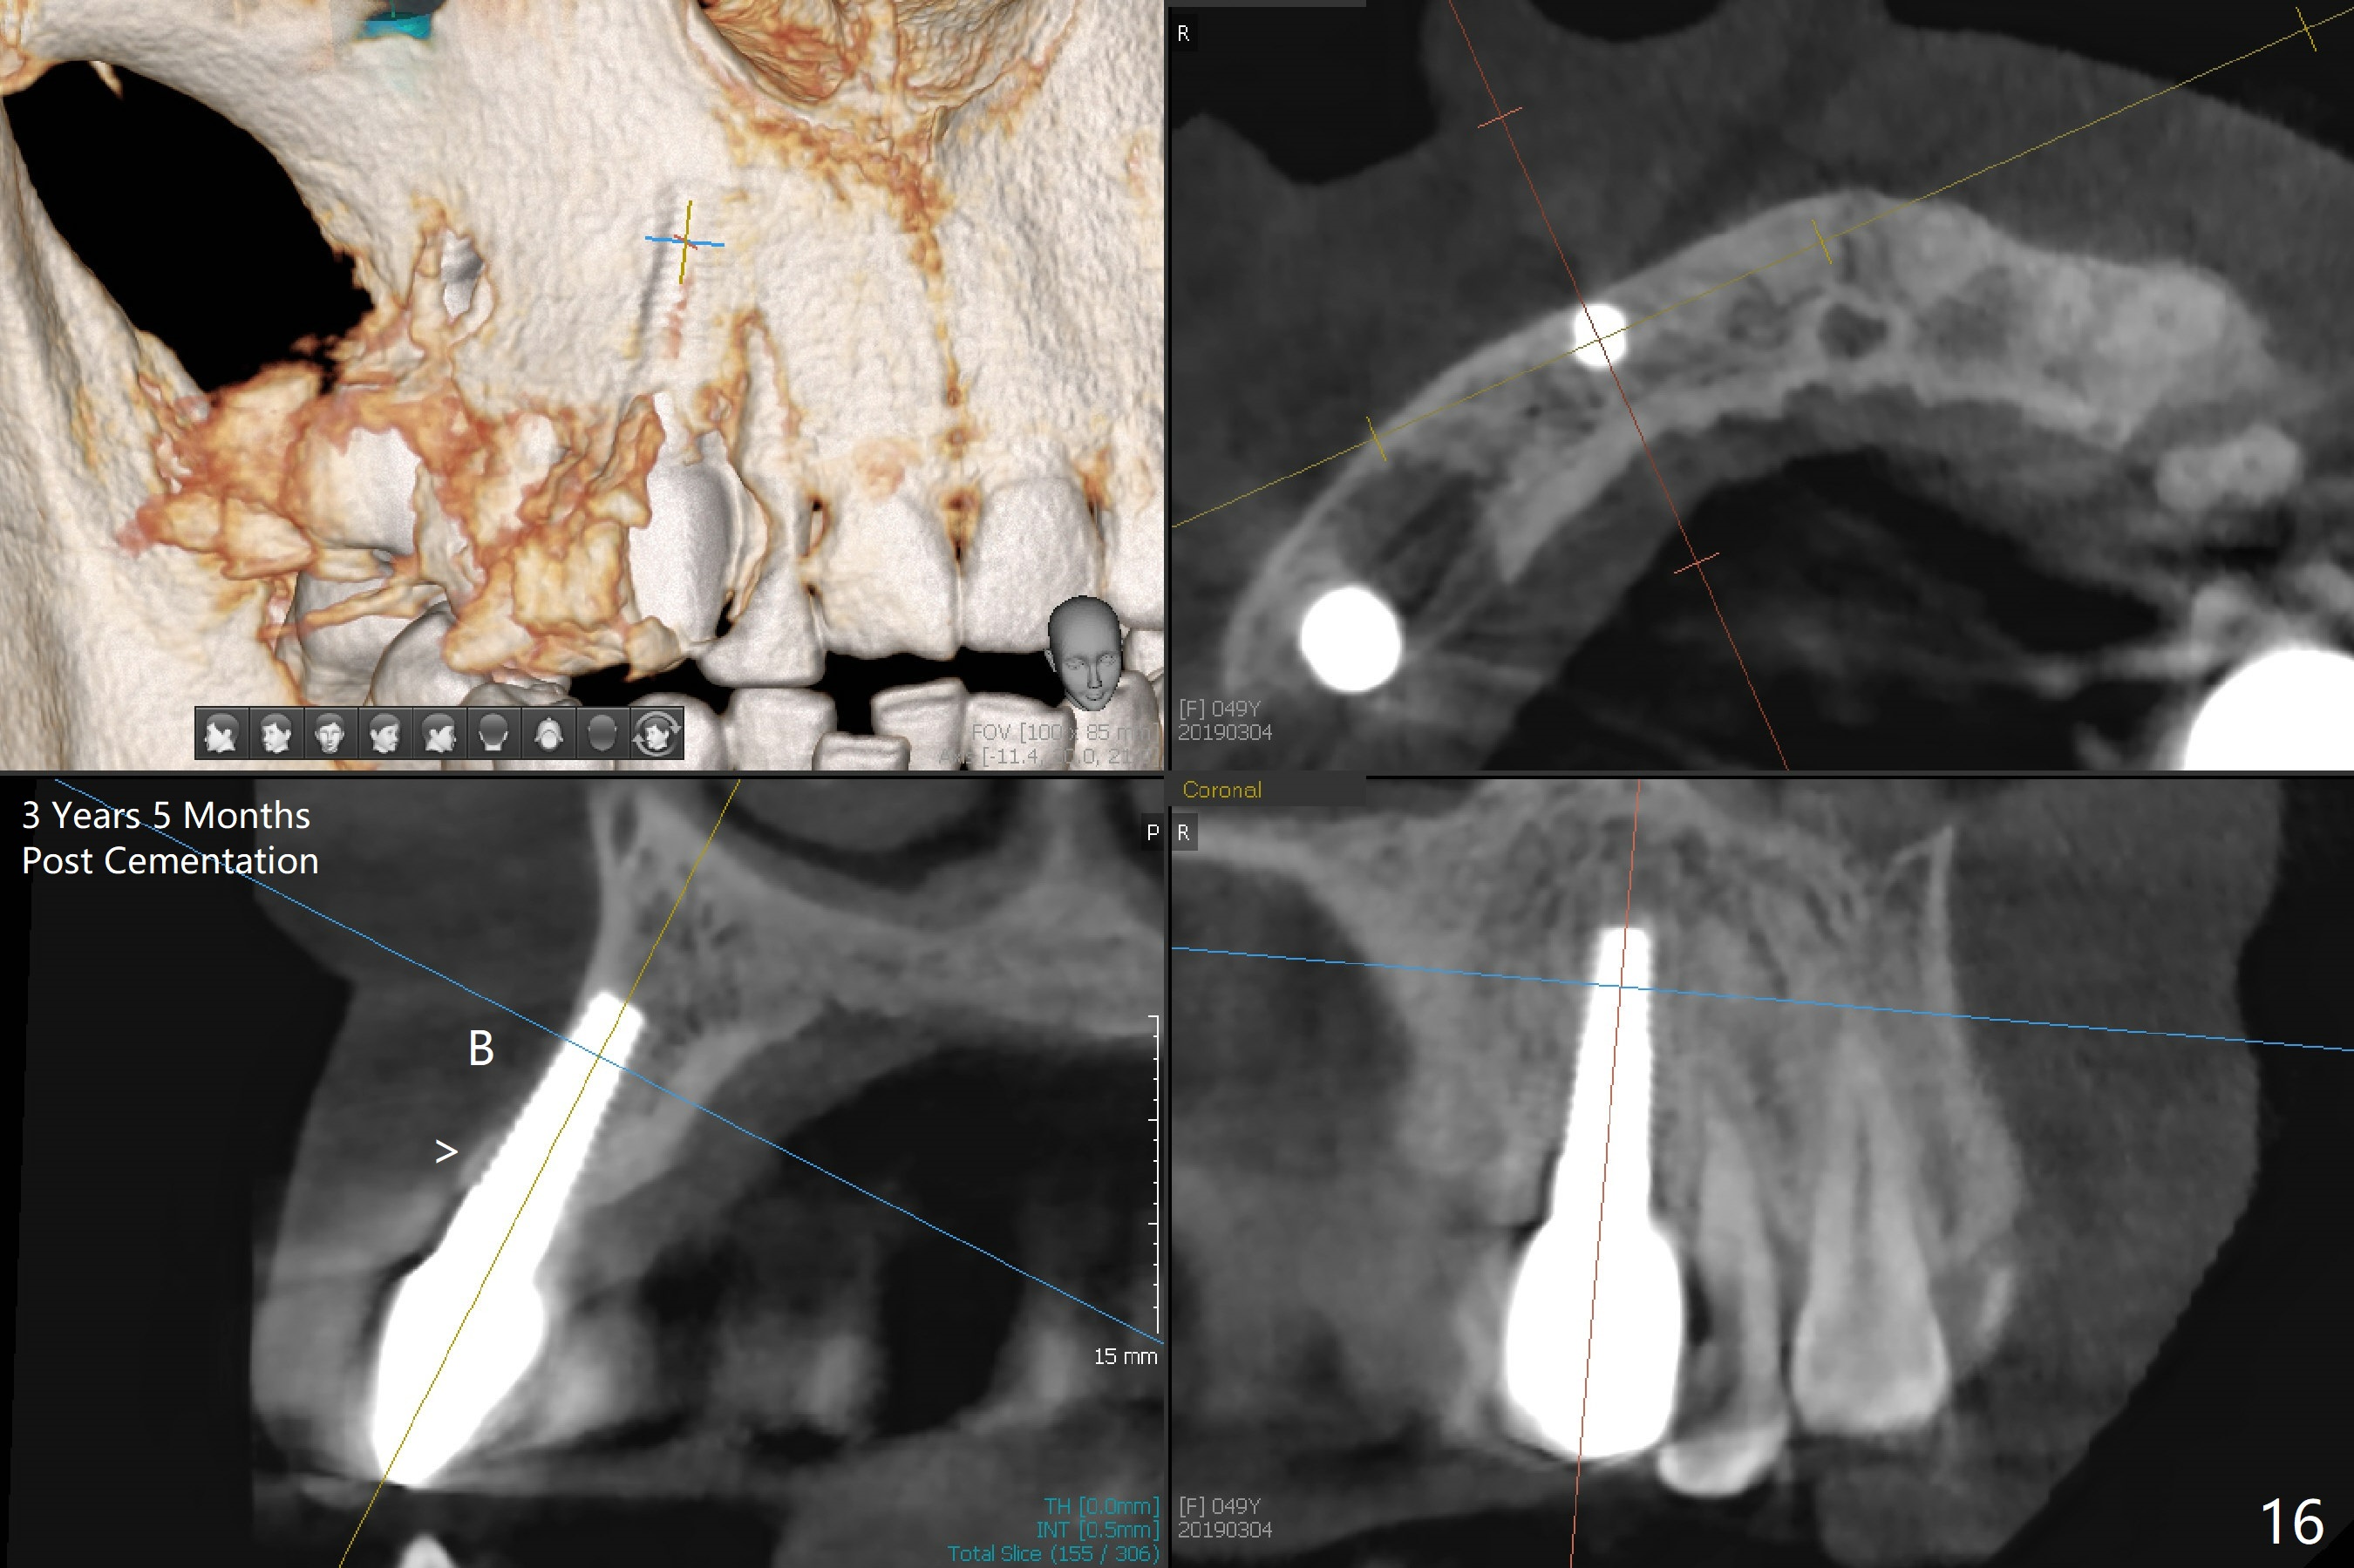

The gingiva is healthy 6 months postop (Fig.13) without buccal plate collapse (Fig.14). The implant and abutment have been prep for final restoration (Fig.15). Although the buccal plate is thin 3 years 5 months post cementation (Fig.16 B), the crest (>) is present, which accounts for no periimplantitis.